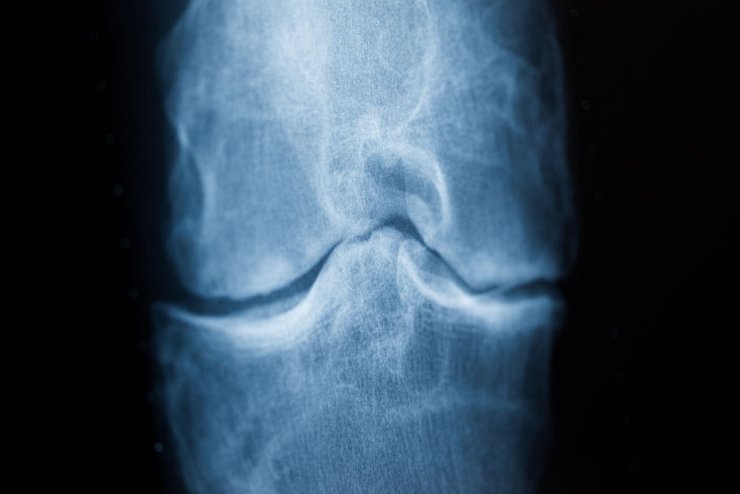

In Deutschland haben laut Deutscher Arthrose-Hilfe etwa fünf Millionen Menschen Beschwerden durch Arthrose. Bei dieser Erkrankung baut sich das Knorpelgewebe im Gelenk ab. Ist der schützende Knorpel zerstört, führt das zu starken Schmerzen. Betroffene können das Knie nicht mehr richtig belasten, treiben oft weniger Sport und sind im Alltag eingeschränkt.

Arthrose tritt meist mit zunehmendem Alter auf und lässt sich nicht heilen. Behandelt wird mit Physiotherapie, Schmerzmitteln und in den schwersten Fällen mit einer Kniegelenkersatz-OP. Hilfreich ist laut der Arthrose-Hilfe Bewegung ohne Belastung, «da dadurch der Gelenkknorpel besser ernährt wird, und das Fortschreiten der Arthrose sich verlangsamt».